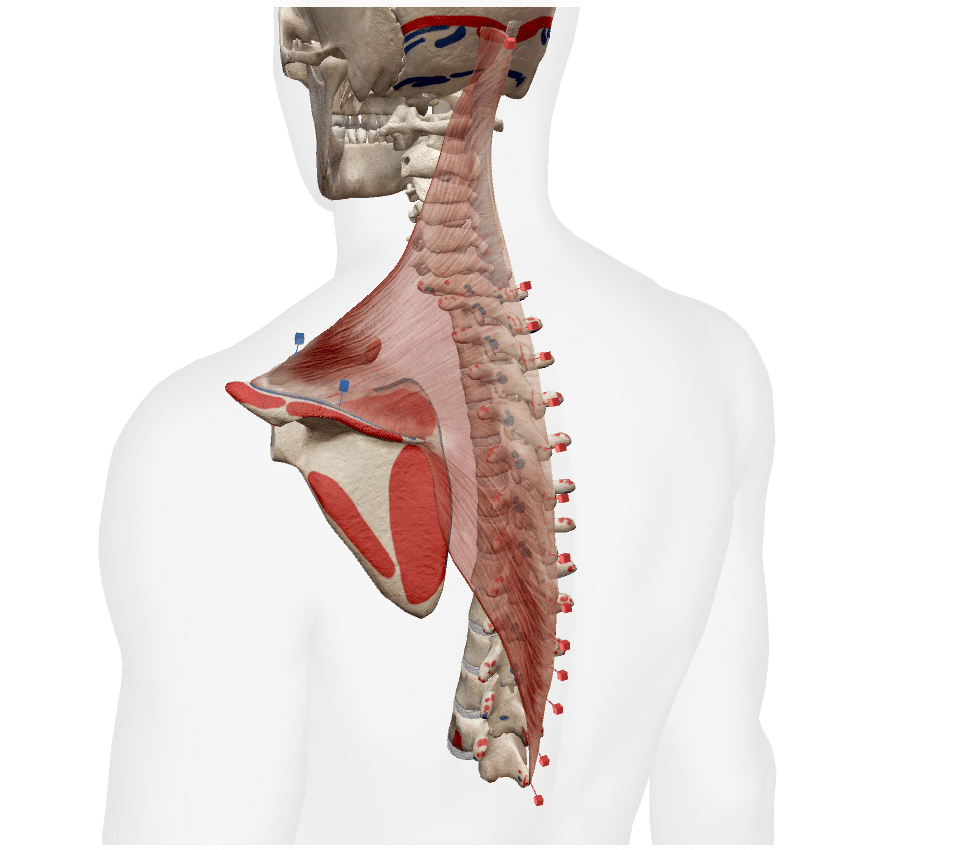

僧帽筋(そうぼうきん)は背部の一番表層部にある筋肉でそれぞれ上部僧帽筋、中部僧帽筋、下部僧帽筋に分類することができます。

起始

C7~C12椎骨の棘突起

停止

鎖骨外側1/3

肩甲骨の肩峰

肩甲棘

上部繊維

肩甲骨の挙上

肩甲骨の上方回旋

頚の屈伸

中部繊維

肩甲骨の内転

肩甲骨の上方回旋

下部繊維

肩甲骨の下制

上部僧帽筋、中部僧帽筋、下部僧帽筋の3つの部分が一緒に働くと肩甲骨は上方回旋と内転動作が同時に起こります。